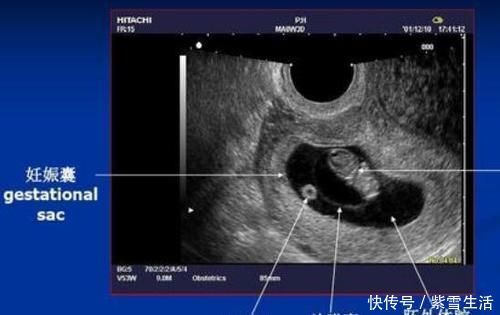

没错的,“孕几个月”、“孕多少周”,是从末次月经第一天就开始算了,并不是受精卵结合的那天,也不是查出怀孕的那天。

因此一般在下次来月经时,发现迟迟不来,一查是 “中招了”,这个时候可能已经怀孕5-6周了。